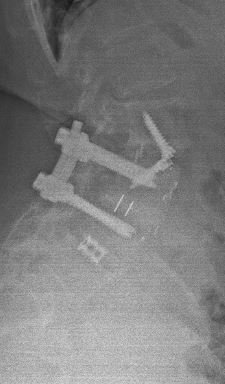

Another example is a young lady who had severe low back pain. Traditionally, fusion surgery through very large incisions would be required. With the new “percutaneous” technique of placement of pedicle screws, we were able to remove her disc through her abdomen and place screws through two small incisions in her back. She is now more than 80% improved.*

We have seen many such results. However, spinal surgery does carry Significant Risks and should not be taken lightly. Surgery, as minimal as it may be, should be utilized as the last option.